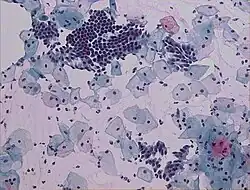

Imagem de um Papanicolau normal

O teste de Papanicolau ou citologia cervical,[1] é um exame ginecológico de citologia cervical realizado como prevenção ao câncer do colo do útero.[2][3]

Consiste basicamente na coleta de células do colo uterino com uma espátula especial e o material é colocado em uma lâmina e analisado inicialmente ao microscópio por um citotécnico, sendo o resultado necessariamente liberado por um médico citopatologista, haja ou não alguma alteração no exame inicial ao microscópio, ou então diretamente por um citotecnologista (biólogo, biomédico ou farmacêutico) e posteriormente revisto por um médico citopatologista para emissão do diagnóstico, apenas nos casos positivos. É um exame citológico, examina a morfologia das células da mucosa do colo do útero, analisa alterações nas células cervicais, chamadas de displasia cervical. A displasia que se desenvolve deve-se a uma infecção causada pelo vírus que se designa papiloma vírus humano (HPV). Este vírus altera de tal forma as células que se podem formar tumores benignos ou mesmo malignos. Duas vacinas já são oferecidas, em clínicas particulares, na maior parte da América Latina, EUA e Europa. No Brasil, desde 2014, a vacina tetravalente (contra quatro tipos de vírus) é oferecida na rede pública para meninas entre 9 e 14 anos e, desde 2017, para meninos de 12 a 13 anos.[5]